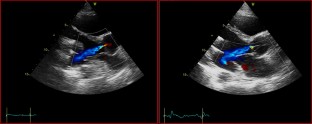

Fig. 1